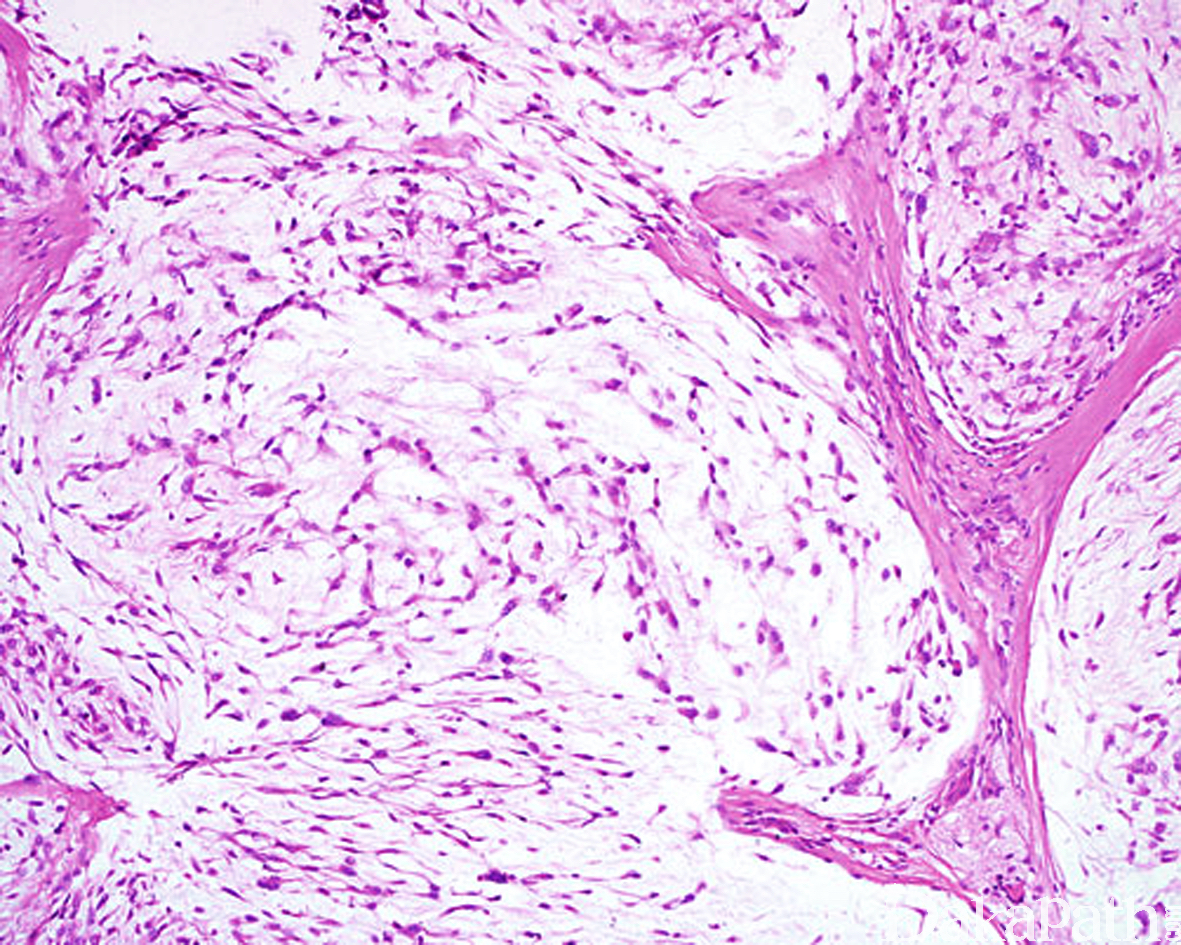

低倍镜下呈大小不等的小叶结构,小叶间为纤维结缔组织间隔;

小叶主要由星状或梭形细胞组成,偶见圆形上皮样细胞;

瘤细胞排列疏松,间质内含有大量的透明质酸或硫酸黏液,AB 染色为阳性;

瘤细胞的胞质呈淡嗜伊红色,常见细长的胞质突起,在小叶或结节的边缘肿瘤细胞常见胞浆内空泡形成印戒样排列;

小叶内的瘤细胞无异型性,核分裂像罕见。